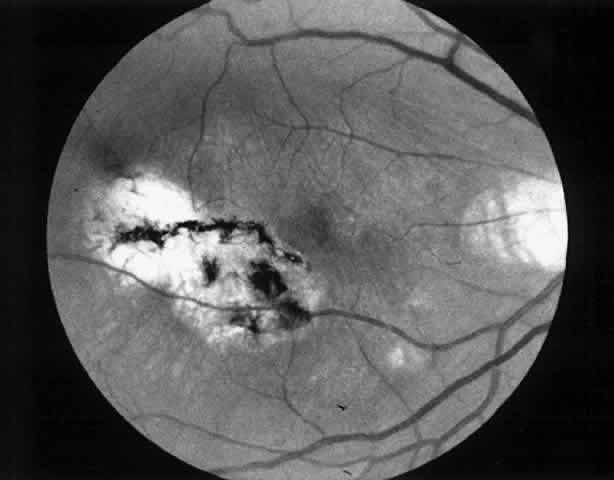

| Patients are examined 1 and 7 to 10 days after surgery to verify that intraocular pressure is acceptable, the retina remains attached, and no infection occurs. Three weeks after surgery, the view is usually adequate for assessment of the presence or absence of subfoveal RPE. Occasionally, residual subretinal blood will obscure the underlying tissues for a longer period of time. Within the first month, angiography is repeated to evaluate for recurrence of neovascularization. Not uncommonly, the site of the original choroidal ingrowth stalk demonstrates recurrent neovascularization. Often this site is not subfoveal and therefore slit lamp laser photocoagulation can be employed to ablate the recurrence. Given the fact that membranes recur in approximately one third of cases within 6 months, close follow-up is essential. |

MEMBRANES ANTERIOR TO RETINAL PIGMENT EPITHELIUM At the present time, we advise surgical extraction of a membrane only if the membrane appears to lie anterior to the RPE. In some cases, this is an easy determination to make preoperatively; in others, it is difficult. We study the macula with stereoscopic viewing at the slit lamp through a 60- or 78-diopter lens or with a contact lens. We also obtain color, stereo, 2× magnified views of the macula for subsequent review. The findings on clinical examination that suggest an anterior location may include the following:

Angiographic findings consistent with membranes anterior to the RPE include the following: